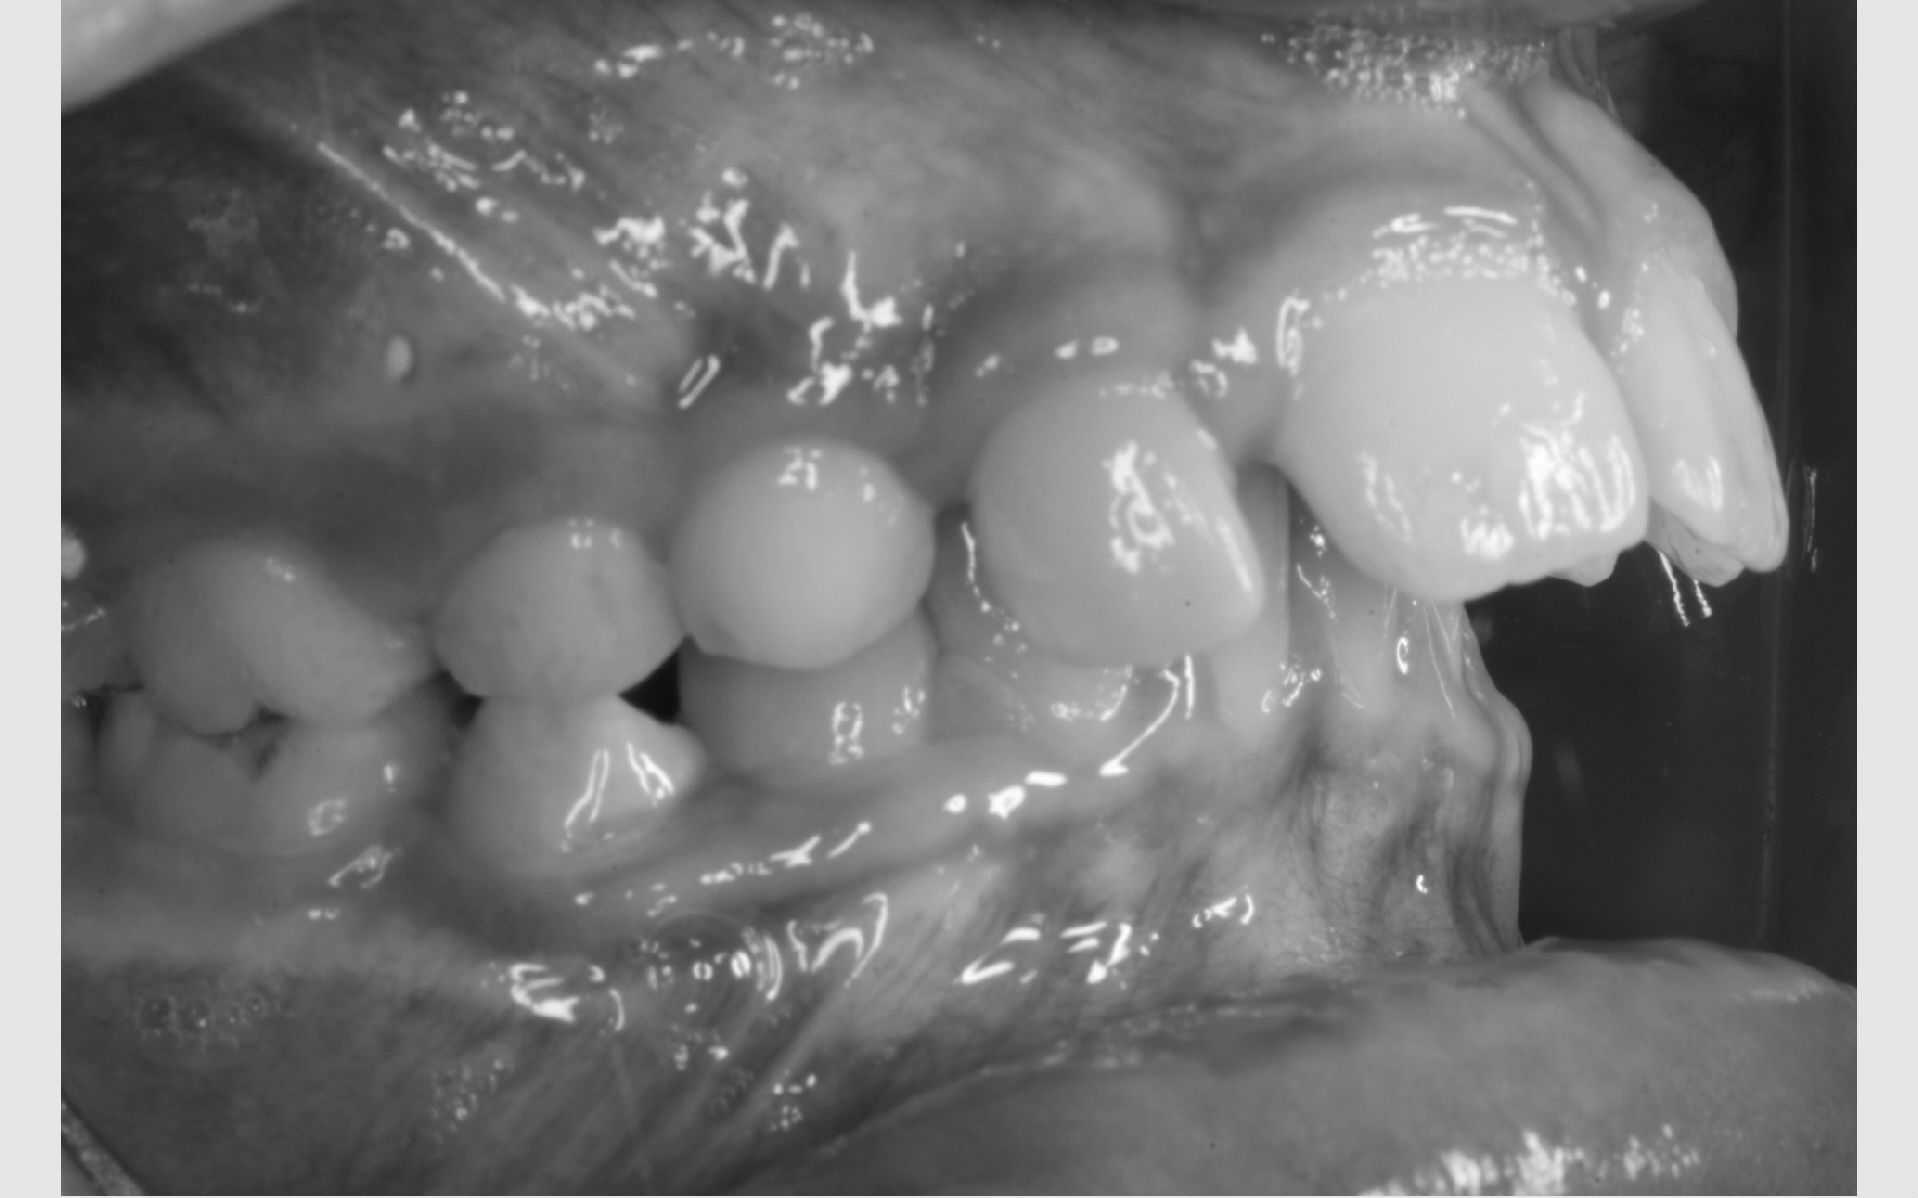

Studiemateriale, består af modeller, fotos og røntgenbilleder af tænder og ansigt. Der bliver også udleveret et helbredsskema, som skal udfyldes på stedet. Det er vigtigt at vide, om jeres barn er sundt og raskt, eller om der er særlige hensyn, vi skal tage - eksempelvis til medicin med videre.

Der bliver taget billeder "udenpå og indeni" samt røntgenbilleder.

Dit barn skal selv holde sine læber til side med en læbeholder, mens tænderne bliver fotograferet. Billederne har følgende formål: